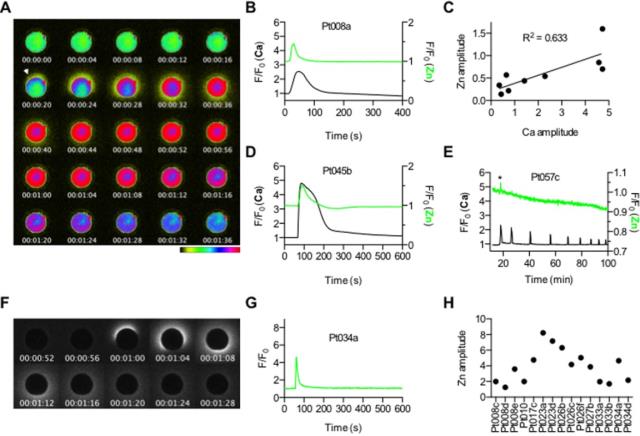

Mucizevi olay daha önce hayvanlarda gözlemlenmişti. Ancak bugüne kadar insanlardaki bu parıltıyı gözlemleyebilen olmamıştı. Bir şaşırtıcı şey ise bazı yumurtalar diğerlerinden daha fazla parlak parlıyor, bu da sağlıklı bir embriyo oluşturabilme konusundaki yeteneklerini gösteriyor.

Bunun öncesinde 2011 yılında yine aynı Northwestern Üniversitesi bilim adamları farelerde sperm yumurtayla birleştiğinde oluşan çinko parıltılarını gözlemlemişti.

Bu olayı nasıl kanıtlayacaklarını yıllarca düşünen bilim insanları 2014 yılında bu olayı ilk defa gözlemlemiş, ve sperm yumurtayı deldiği anda salgılanan serbest duruma geçen milyarlarca çinko atomunu seyretmişti.

Yeni bir flörasan algılayıcı kullanarak canlı hücrelerdeki çinko atomu hareketlerini takip eden bilim ekibi, yumurtadaki çinko depolama yeteneğini fark etti. Yaklaşık 8000 değişik küçük haznede depolanan 1 milyon civarında çinko atomu döllenme gerçekleşince havai fişek gibi ateşleniyor. Döllenmenin ardından 2 saat boyunca bu olay devam ediyor. Kaynak: Süperileri.com, Nature.com